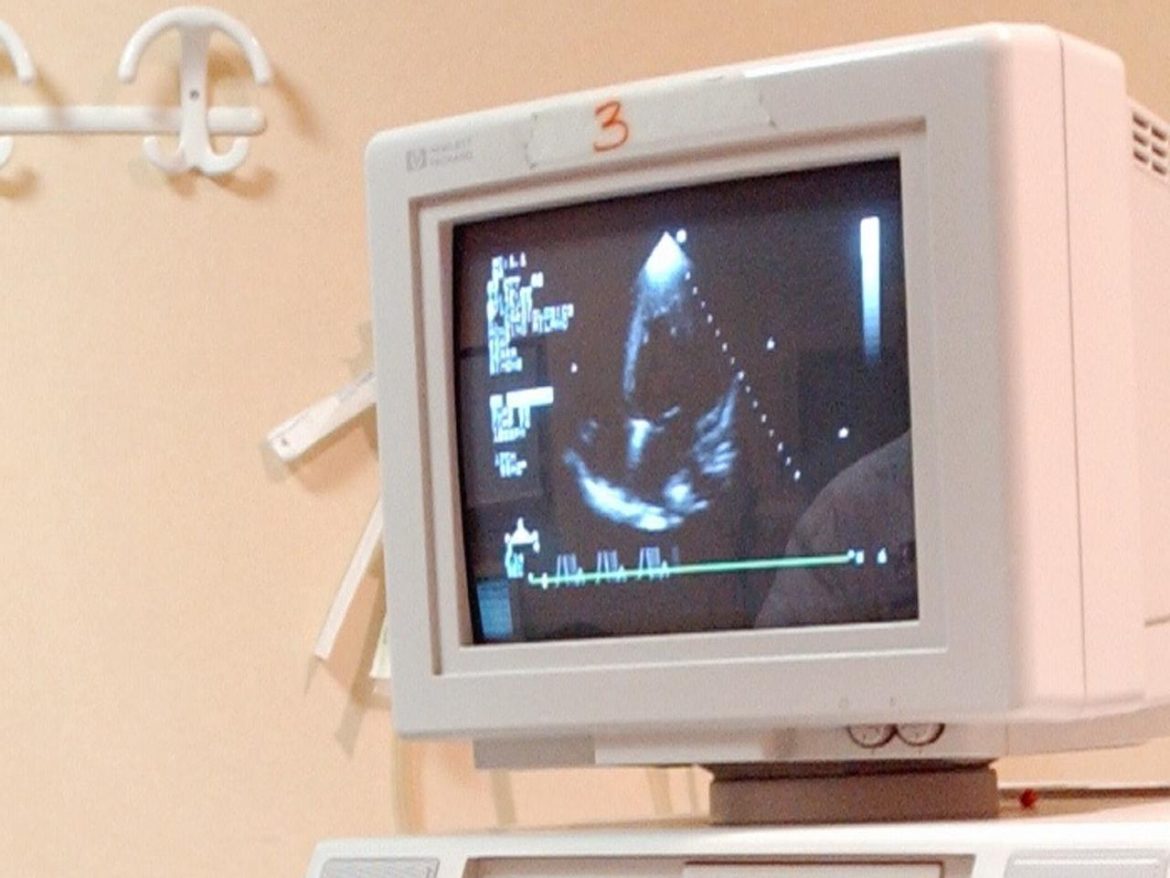

Milano, 23 ott. (Adnkronos Salute) – Sono 35 i cuori artificiali impiantati con successo al Centro cardiologico Monzino di Milano, di cui negli ultimi 18 mesi 8 ‘HeartMate 3’, “il dispositivo più avanzato a livello internazionale”. Si tratta infatti del “primo Vad (Ventricular Assistance Device) completamente impiantabile – informano dall’Irccs meneghino – che utilizza la tecnologia di levitazione magnetica, progettata per minimizzare le complicanze e ripristinare il flusso sanguigno”.I Vad – ricordano gli esperti del Monzino – hanno la funzione di ‘pompa del sangue’ e contribuiscono in toto o in parte alla funzione del ventricolo, per lo più il sinistro, di diffondere il sangue in tutto l’organismo. Si tratta quindi di dispositivi miniaturizzati, delle vere mini-pompe, che vengono posizionati all’interno del torace per assistere il cuore nella sua azione propulsiva.”Lo scompenso grave, o insufficienza cardiaca – spiega Piergiuseppe Agostoni, direttore della Cardiologia critica del Monzino e professore di Cardiologia all’università Statale di Milano – è l’incapacità del cuore di contrarsi e dilatarsi in maniera sufficiente per svolgere le sue funzioni vitali. Fino agli anni ’60 l’unica terapia possibile era il trapianto di un nuovo cuore. Tuttavia il trapianto presenta ancora oggi limiti importanti, quali l'(in)disponibilità dell’organo o la selezione del paziente. Per questo la ricerca si è concentrata sui Vad e quelli attuali, come HeartMate 3, funzionano con tecnologie di propulsione del sangue nuove, che sfruttano i campi magnetici, garantendo maggiore durata e sicurezza rispetto al passato e soprattutto minor rischio di complicanze trombo-emboliche. Poco ingombranti rispetto ai modelli precedenti, funzionano grazie a batterie che si portano in vita come una cintura. Sono in corso di sperimentazione anche ricariche wireless, senza fili e senza bisogno di batterie esterne”.L’impianto di un Vad – sottolineano dal Monzino – prevede un team multidisciplinare e un fondamentale lavoro di squadra, che segue il paziente dalla selezione al follow-up nel tempo. Questo gruppo coinvolge il cardiologo esperto di scompenso cardiaco avanzato per la selezione e follow-up del paziente, il cardiologo esperto in imaging ed emodinamica, lo psicologo, l’anestesista rianimatore e il cardiochirurgo.”Le indicazioni al Vad sono molteplici – illustra Agostoni – e vanno da quelle temporanee in attesa di un cuore da trapiantare a quelle in cui il Vad è definitivo, quando un trapianto non è possibile. Questo significa, ad esempio, pazienti con problemi di età o comorbidità. Pertanto il Vad non è più considerato solo la ‘soluzione ponte’ di passaggio al trapianto, ma una terapia di destinazione che può sostituirsi al trapianto stesso. Le sue performance, e di conseguenza i benefici per il paziente portatore, vanno di pari passo con l’evoluzione tecnologica che è in continuo miglioramento. Già adesso la sopravvivenza media dei pazienti con Vad di lunga durata è di circa 5 anni, a fronte di una attesa di 6 mesi. Si tratta ovviamente di una media statistica, perché tutto dipende dalle condizioni specifiche di ogni paziente candidato all’impianto. Ma è indubbio che più passa il tempo, più questi dati migliorano per tutti”.